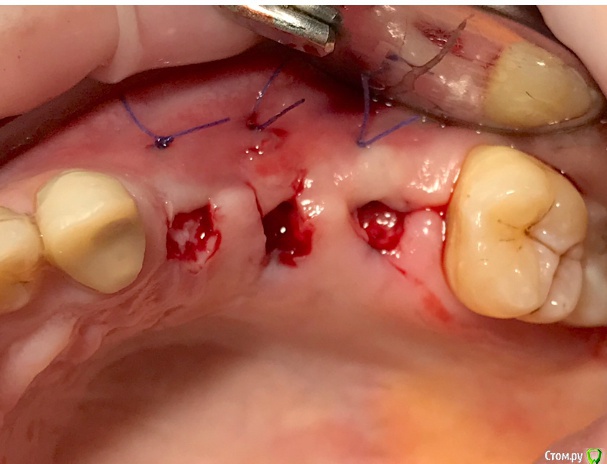

колесников Опубликовано 20 августа, 2019 Автор Поделиться Опубликовано 20 августа, 2019 Очередной случай тоннельной пластики альвеолярного гребня. Был небольшой бонус в виде лунки 26го зуба с дефектом вестибулярной стенки и оас. Лунка консервирована и закрыта «быстрым Ноймайером»,24,25 тоннельный графтинг. Графт тот же,шурос кортикальный без добавок.Контроль и имплантация через 4 мес,через неделю фиксация временной реставрации. Через 2-3 проверим на состоятельность. 4 Ссылка на комментарий